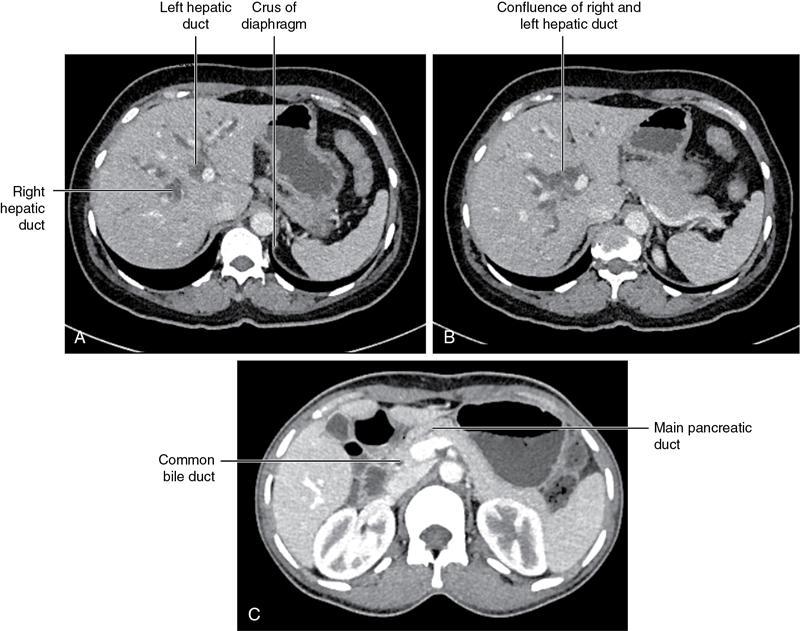

CROSS SECTIONAL ANATOMY OF ABDOMEN Satya Jha NORMAL ANATOMY OF ABDOMEN AND PELVIS Amandeep Singh The two major surfaces: The anterior and posterior layers of the coronary ligament converge on bare area (not covered by peritoneum). Its right and left margins form the right and left triangular ligaments. The right triangular ligament extends toward the diaphragm and separates right subphrenic space from right subhepatic space. The left triangular ligament gives tracts extending to the diaphragm and falciform ligament and does not compartmentalize the left subphrenic space. Ligamentum teres or the obliterated umblical vein is contained in falciform ligament which attaches the liver to anterior abdominal wall. The main portal vein, the proper hepatic artery and the common bile duct are contained within investing peritoneal folds of hepatoduodenal ligament at the porta hepatis (Fig. 7.2.2.1). Liver is divided into eight segments which are functionally independent and have their own vascular supply and biliary drainage. Arterial circulation: The branches of the hepatic artery accompanying the portal veins. Hepatic venous system: The right, middle, and left hepatic veins draining into IVC (Figs. 7.2.2.2 and 7.2.2.3). The gallbladder is a blind pear-shaped muscular membranous sac which is an embryologic derivative of the foregut, is a pouch lying along the undersurface of the liver. The gallbladder fossa is located in the plane of the interlobar fissure, which lies between the right and left hepatic lobes. Its major function is to store and concentrate bile which is produced by the liver. It measures approximately 4 cm in diameter when it is normally distended. Gallbladder is a smaller tubular structure in contracted state. The normal gallbladder wall thickness ranges from 1 to 3 mm. The gallbladder is divided into the fundus, body and neck. Infundibulum is present in the region of neck of the gallbladder, which is called the Hartmann pouch, where gallstones are usually impacted. Intrahepatic biliary radicles (IHBRs) scattered throughout the liver get confluent towards the hilum. They unite to form the right and left main hepatic ducts which further unite to form common hepatic duct (CHD) at the hilum. Common bile duct is formed by the union of cystic duct with common hepatic duct. The main pancreatic duct is joined with the common bile duct to form the ampulla of Vater at the major duodenal papilla (Figs. 7.2.2.4 and 7.2.2.5). Pancreas is located in anterior pararenal space of retroperitoneum anterior to perirenal (Gerota’s) fascia and posterior to parietal peritoneum. It is divided into head, uncinate process, neck, body and tail from right to left. Pancreas lies anterior to portal vein, which marks the point of transition between the body and neck. The region between head of pancreas and second and third parts of duodenum is known as the pancreatic groove. In postnephrectomy cases or with agenesis of kidney or ectopic kidney, pancreas moves posteriorly to partially fill in the empty renal fossa; its soft tissue density should not be mistaken for recurrent tumour. It is located in the pancreatic groove and is bounded superiorly by the duodenal bulb, laterally by second portion of duodenum, inferiorly by third portion of duodenum, medially by superior mesenteric vein and anterior to inferior vena cava. It is a wedge or wedge shaped lying posterior to superior mesenteric artery and vein. It is an imaginary junction between the head and body and lies directly over the junction of the splenic vein and superior mesenteric vein. It is located posterior to the lesser sac and anterior to the aorta, left adrenal gland, left kidney, and renal vessels and runs obliquely upward to the left of the superior mesenteric vessels. It is situated median to the colonic flexure and anterior to the left kidney. It is located in close proximity to the splenic hilum without a notable relation with the body of pancreas. It is seen anterior to the left kidney and median to the colonic flexure. The distal part of the tail passes between the peritoneal layers of the splenorenal ligament (Fig. 7.2.2.6 and 7.2.2.7).